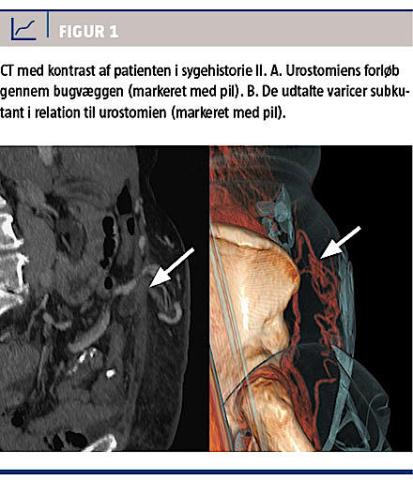

med hypertensio arterialis og atrieflimren og havde pacemaker, fik i 2006 konstateret blærecancer (pT3N2M0) og blev primært behandlet med cystektomi, bækkenrømning og anlæggelse af Brickerblærestomi. To år efter primæroperationen oplevede patienten det første tilfælde af blødning fra stomikanten. Dette blev tolket som værende betinget af dysreguleret antikoagulans (AK)-behandling (international normaliseret ratio: 4,3) og leverintoksikation på mulig alkoholisk basis. AK-behandlingen blev seponeret, og blødningen stoppede. Herefter havde patienten ikke indlæggelseskrævende blødninger i tre år før sommeren 2011, hvor hun blev indlagt til optransfundering og igen tre måneder senere til ultralydvejledt ligering af en dilateret vene i relation til stomien. Patienten blev indlagt igen i december 2012 grundet blødning og anæmisk betinget nonoligurisk nyreinsufficiens. Blødningen stoppede spontant, og nyrefunktionen rettede sig på blodtransfusion. I januar 2013 blev hun udredt for åndenød og overhydrering, hvor der blev påvist nytilkommen svær trikuspidalinsufficiens, som blev opereret. Umiddelbart herefter blev hun indlagt på urologisk afdeling med svær blødning i Brickerblæren (hæmoglobinniveau: 4,8 mmol/l). Hun blev primært behandlet med kompression via kateter, men pga. recidiverende svære blødningstilfælde valgte man kirurgisk at revidere Brickerblæren, og man exciderede stomiens distale 1,5 cm inklusive et 5 × 7 mm stomalt ulcus, som ved looposkopi var blevet fundet tidligere under indlæggelsen. Ved tremånedersfollowup var der ingen nytilkomne blødningsepisoder. I Figur 1 illustreres hendes parastomale varicer.